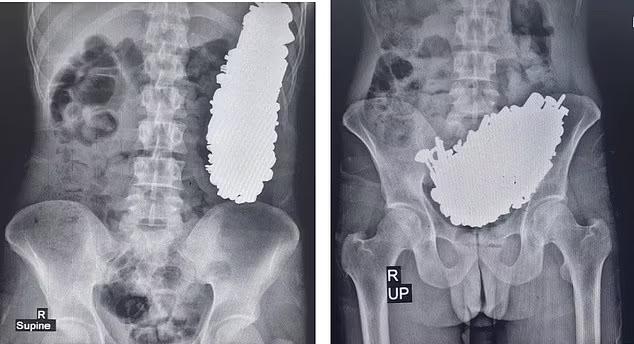

在伊朗西南城市阿瓦士市,一名37岁的男子因腹痛和呕吐症状去医院检查。结果,x光片显示,他的胃里有螺丝、铭牌、钥匙和螺母等金属物品。此外,内窥镜检查还证实了金属物体在其体内的存在。

▲X光片,左边是仰卧状态,右边是直立状态。

医生迅速将该男子送到手术室,取出452个“螺丝、螺母、钥匙等金属物品和石头”。通过在他的胃里切开一个嘴,总重量约为2.9。KG。这类金属物体堵塞了该男子的胃出口,导致他长期胃痛,经常呕吐,不能吃东西或喝水。